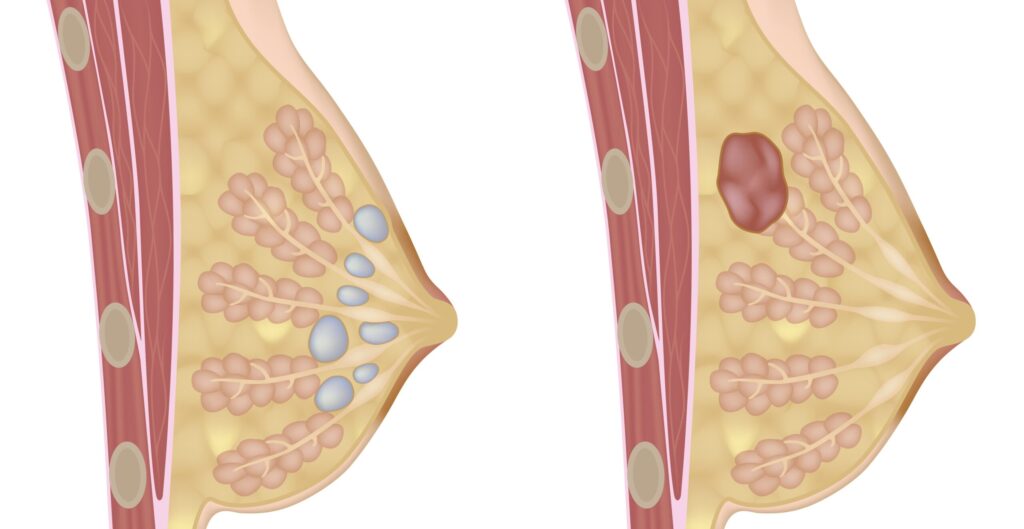

Mamas: Cistos e Nódulos – Diagnóstico e Cuidados

Você já sentiu um caroço na mama durante o autoexame ou recebeu um diagnóstico de cisto ou nódulo e ficou preocupada? Se isso aconteceu, saiba que você não está sozinha. Como mastologista, vejo diariamente mulheres que chegam ao consultório assustadas com alterações em suas mamas. A boa notícia é que a maioria dessas alterações é […]